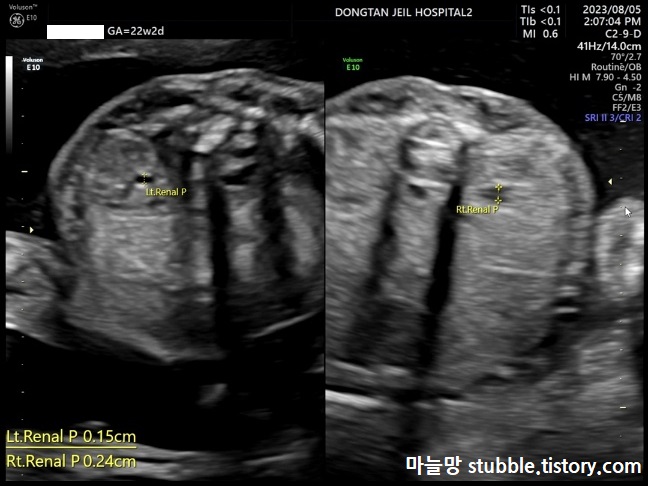

7. 신장 잘 형성되어 있는지의 여부 (Renal)

이제 전문가가 아닌 이상 어려워요.